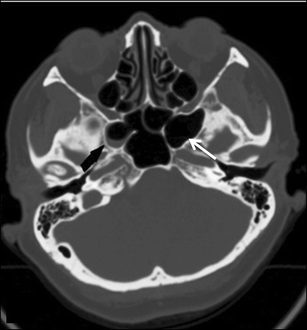

Soft tissue sphenoid sinus. Fluid right middle ear cavity and right mastoid air cells suggesting an active inflammatory process. Coronal reformatted image in a soft-tissue window from a noncontrast CT scan shows a soft-tissue mass centered on the sphenoid sinus with dehiscence of the planum sphenoidale arrow. According to his expertise he said the bones that surround the dark area hole of the sphenoid sinus - the one on the left side brokedisinergrated whatever and the soft tissue spilled into that area. Soft tissue sphenoid sinus

The CT scan exhibited a non-enhancing 3 5 cm soft-tissue mass centered in the sphenoid sinus and extending into the left ethmoid sinuses and the pterygopalatine fossa as well as the middle cranial fossa Figure 1. MR better images the contents of the cephalocele showing CSF and herniated meninges andor brain tissue. Soft tissue densities in the normally air filled mastoid middle ear and sinus cavities indicates there is some type of chronic long term inflammation in those areas. Soft tissue sphenoid sinus

Isolated sphenoid sinus disease is unusual and one should at least consider the possibility of a cephalocele with a rounded soft tissue density in the sphenoid sinus. Large soft tissue mass in the masticator space asterisk. Here we explore what causes sphenoid sinusitis and how to deal with it. Soft tissue sphenoid sinus

Wha does this mean soft tissue densities within mastoid cells middle ear cavity and sphenoid sinus and calcific density in brain paren occipital reg. Surrounding circumferential hypoattenuating mucosal thickening is usually present indicating chronic sinusitis. 13 CT shows fungus ball as a high-density mass with calcification. Soft tissue sphenoid sinus